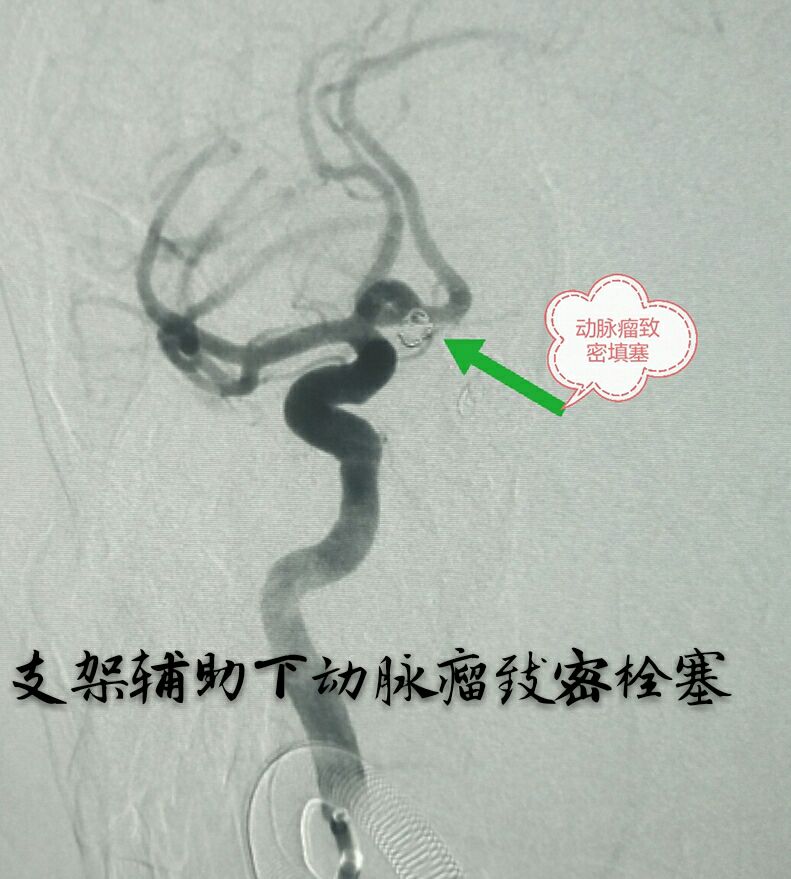

病例三:87岁女性患者,突发头痛、恶心、呕吐,头颅CT示蛛网膜下腔出血量较大,DSA示左侧颈内动脉后交通段动脉瘤,宽颈,形态不规则,有子囊

支架辅助下动脉瘤致密栓塞,因后交通动脉从瘤体发出,并靠近子囊,无法保护,决定牺牲同侧后交通动脉,好在同侧大脑后动脉P1段存在,最终无任何症状体征